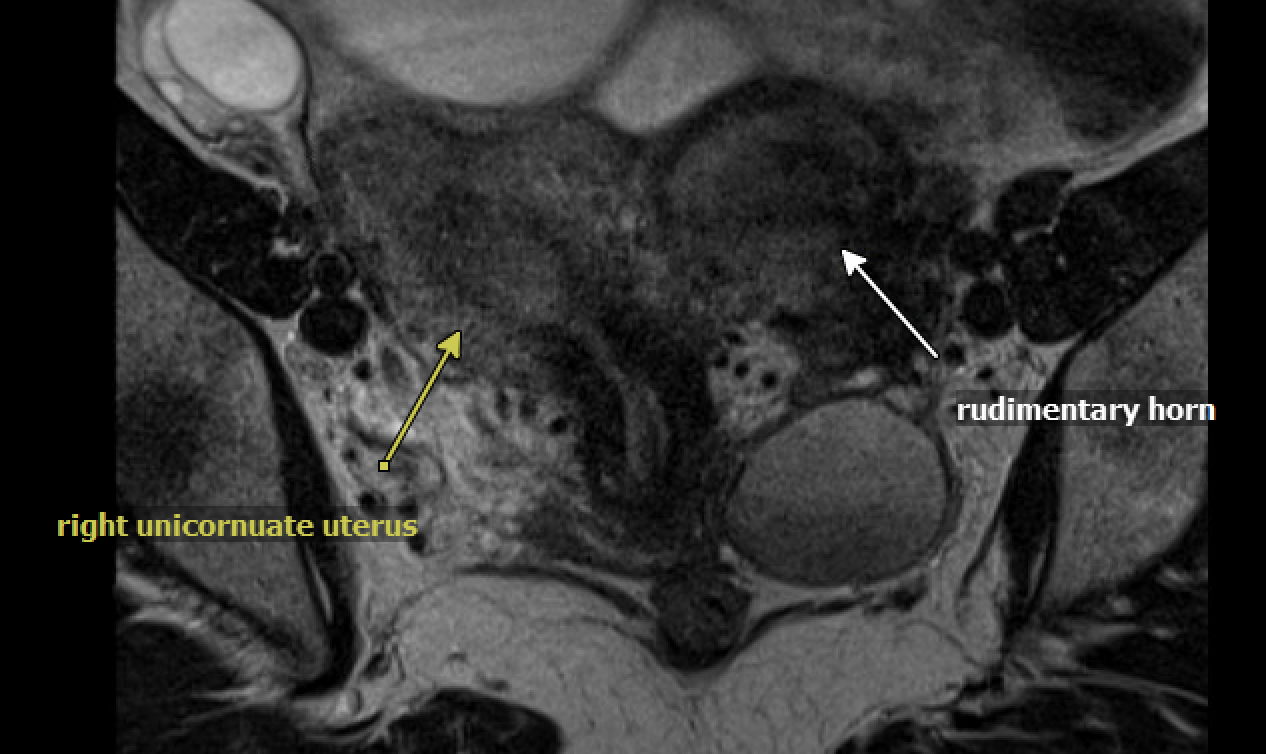

Sage was born with a rare uterine anomaly called unicornuate uterus with a rudimentary horn, which impacts about 0.03% of the population. This means that Sage’s uterus primarily developed on the right side of her body, while the left side only partially developed.

An MRI of Sage’s lower abdomen showing her anatomical anomaly: unicornuate uterus with a rudimentary horn.

Caption: An MRI of Sage’s lower abdomen showing her anatomical anomaly: unicornuate uterus with a rudimentary horn.